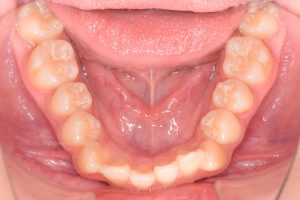

下あご

0000000005

0000000027

0000000078

1期治療開始時(2024年3月)

2期治療開始時(2024年11月)

保定開始時(2025年1月)の写真です。